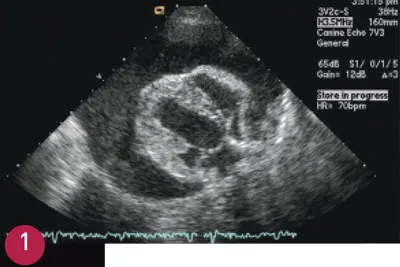

In my experience, the highest elevations are in animals with suspected or confirmed myocarditis. Increased cTnI has been reported with myocarditis due to infectious causes, such as babesiosis or ehrlichiosis.4 Elevations in cTnI have been shown in dogs with pericardial effusion due to hemangiosarcoma.5 Pericardial effusion is the most common indication for measuring cTnI in my clinical practice. In addition, cTnI is a useful additional diagnostic test in an older dog with pericardial effusion and no obvious mass on echocardiography. The finding of an elevated cTnI in this patient might suggest a small and difficult-to-visualize mass (Figure 1).

FIGURE 1

Echocardiogram of 10-year-old spayed female golden retriever with pericardial effusion and cardiac tamponade. An elevated cTnI increases the likelihood of neoplasia when a mass cannot be visualized on echocardiography.